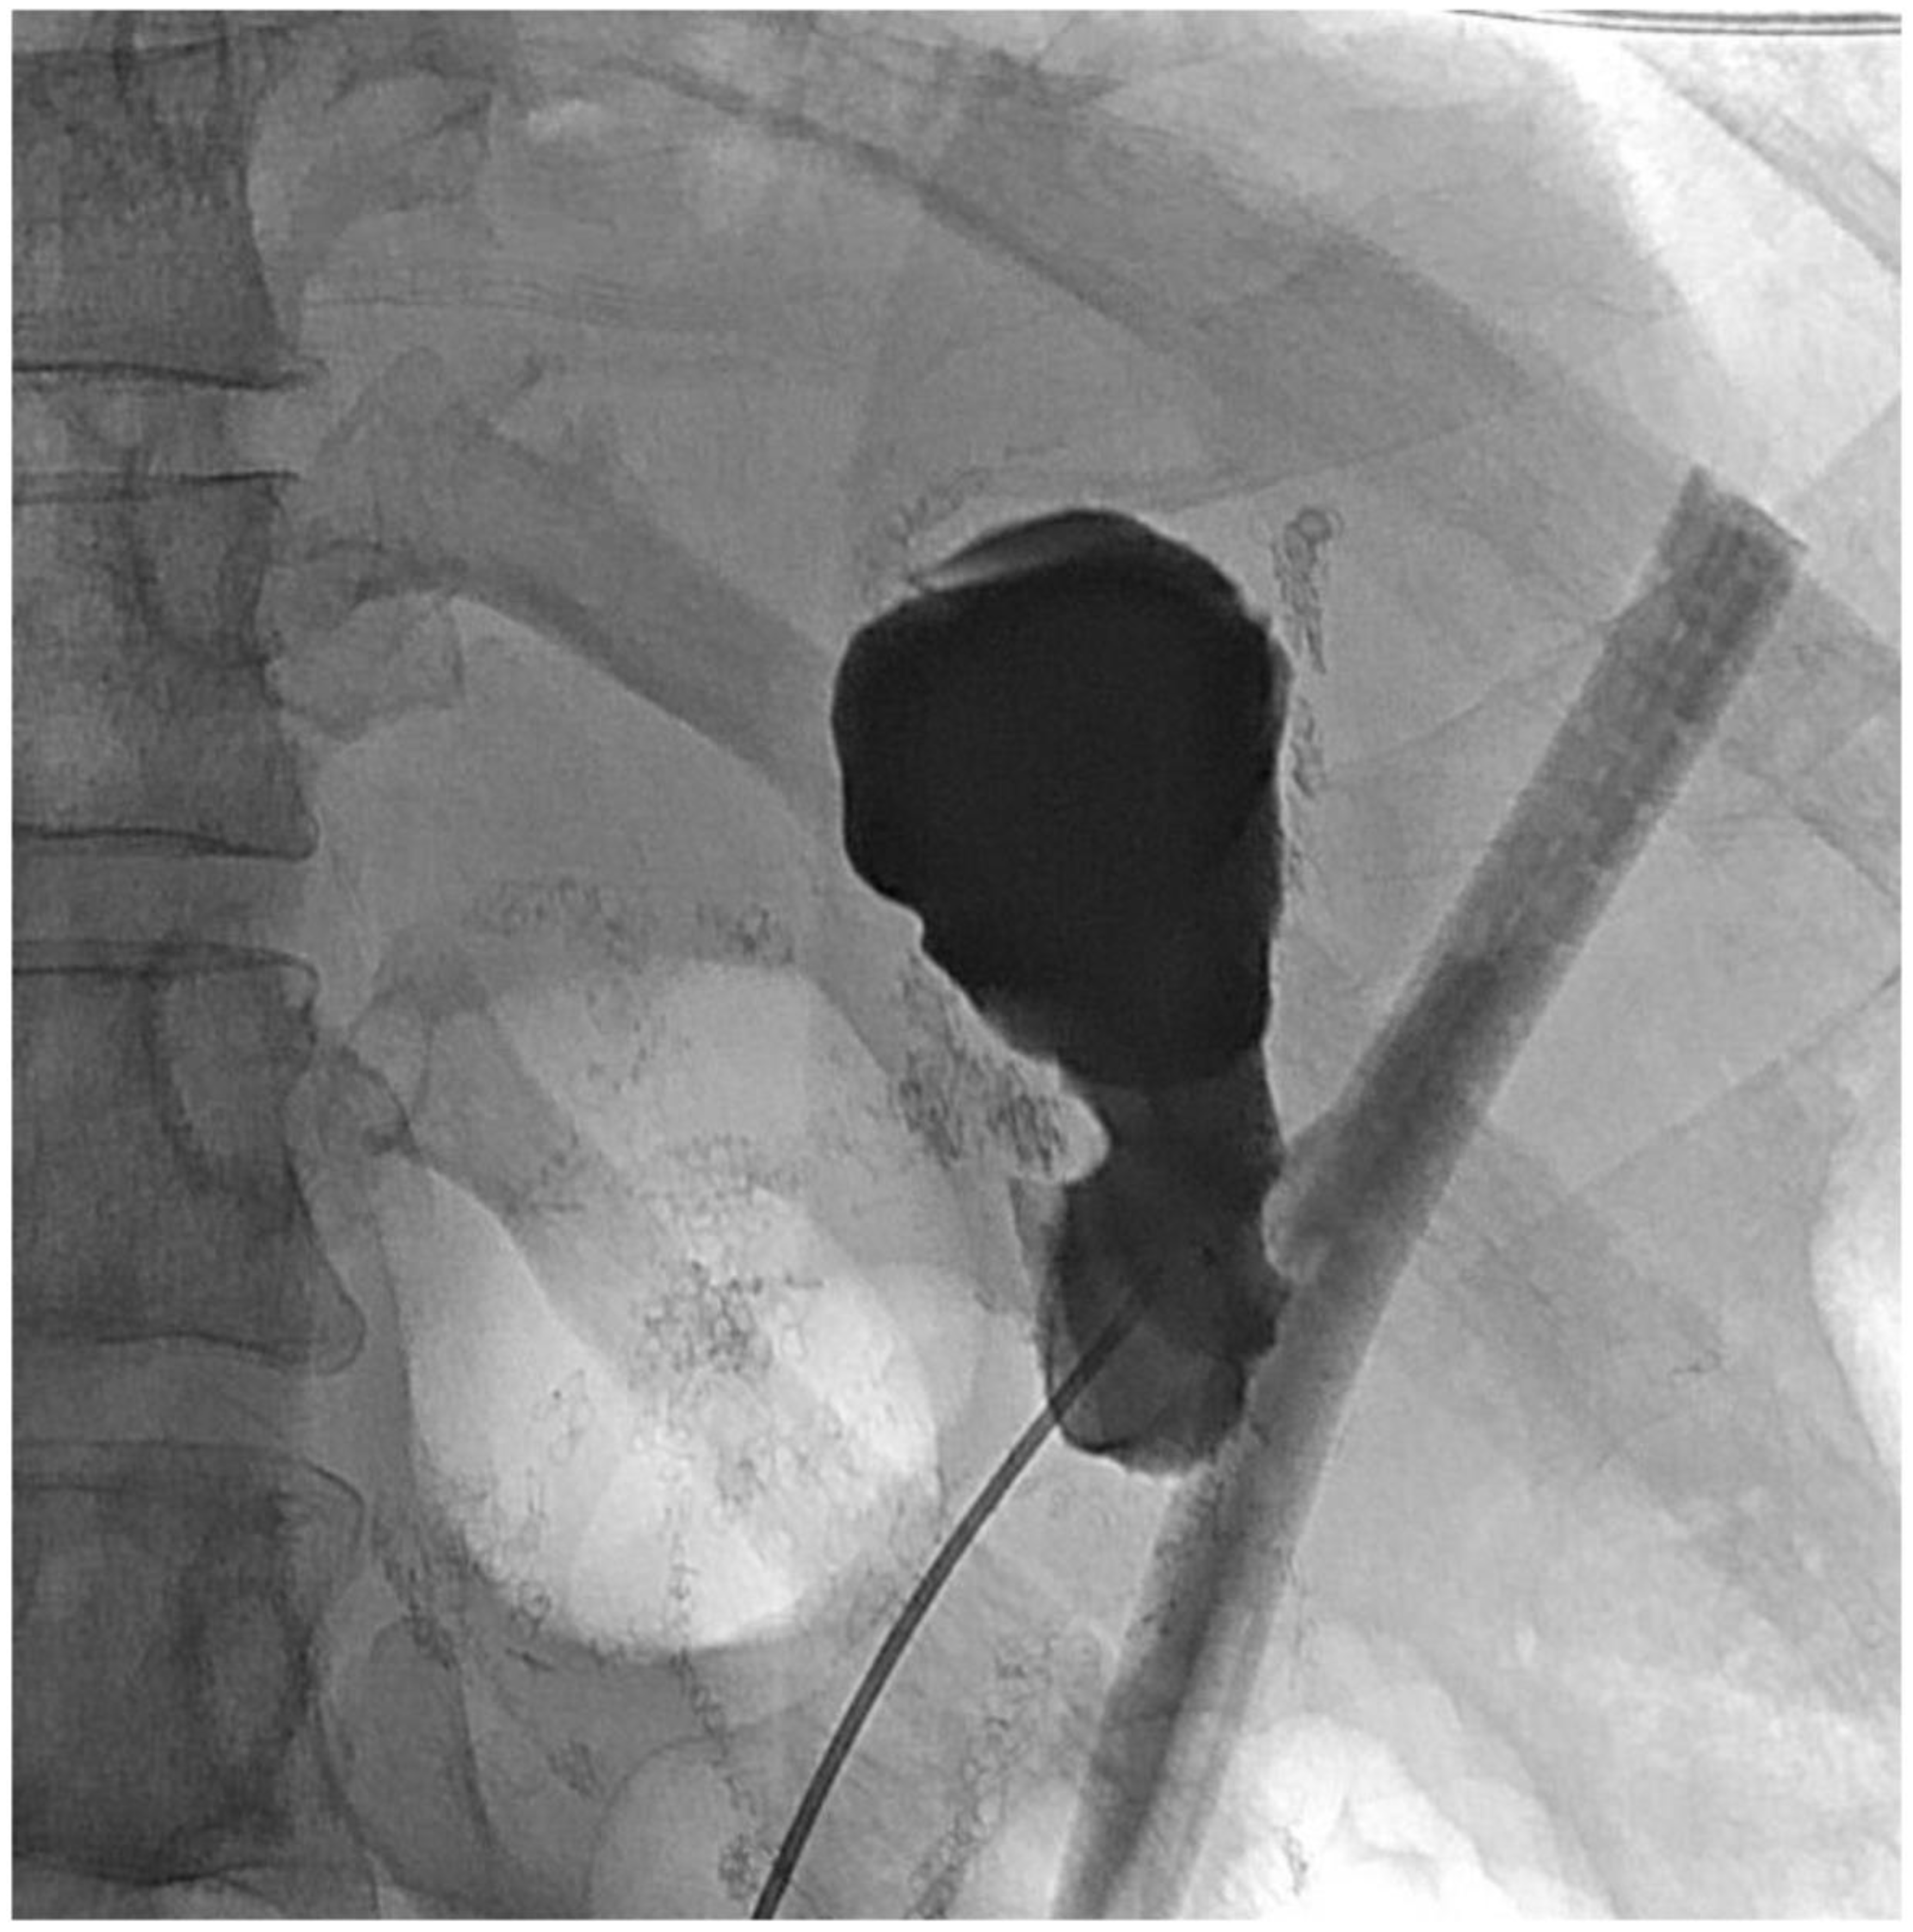

2. Detailed Case Description